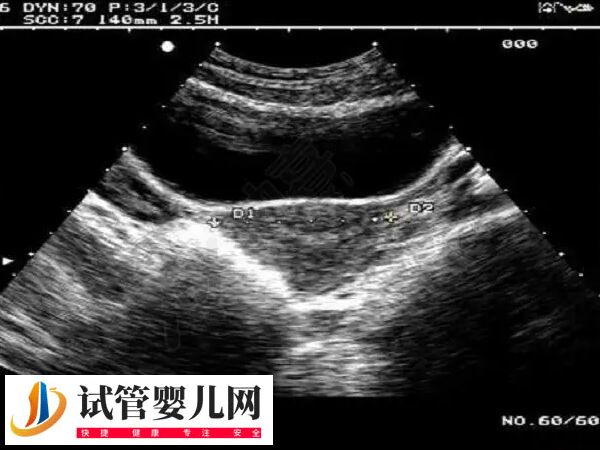

3、输卵管积水

输卵管积水的存在,会干扰到子宫内膜与胚胎的接触,影响胚胎的着床;输卵管积水临近卵巢,会对卵巢形成压迫作用,导致卵巢内的卵泡发育受到影响;输卵管积水对内膜的损伤往往是很大的,伤害子宫内膜的同时,还会加重宫腔的炎症,使宫腔环境进一步恶化。